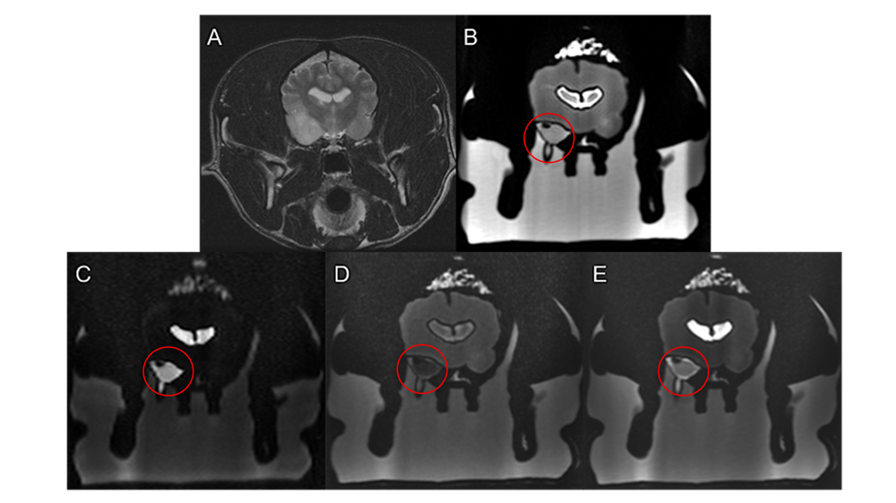

MRI scan of the dog (A) and the printed phantom with various analyses highlighting the tumor in red circle (B,C,D,E)

Initial scans of the printed models revealed remarkable fidelity between the printed anatomy and Charlotte’s original imaging data. Hounsfield Unit (HU) values from the CT scans of the model closely mirrored those of the real patient, demonstrating material accuracy and confirming that the prints could be used for realistic, scan-compatible planning.

Several versions of the model were produced using Stratasys' Digital Anatomy solution to allow for CT and MRI imaging. Axial3D handled the intricate segmentation, combining MRI data for soft tissue structures like ventricles and the tumor with CT data for bone and muscle detail. To maximize training potential, the team added a second, artificial tumor to the model for biopsy practice purposes.